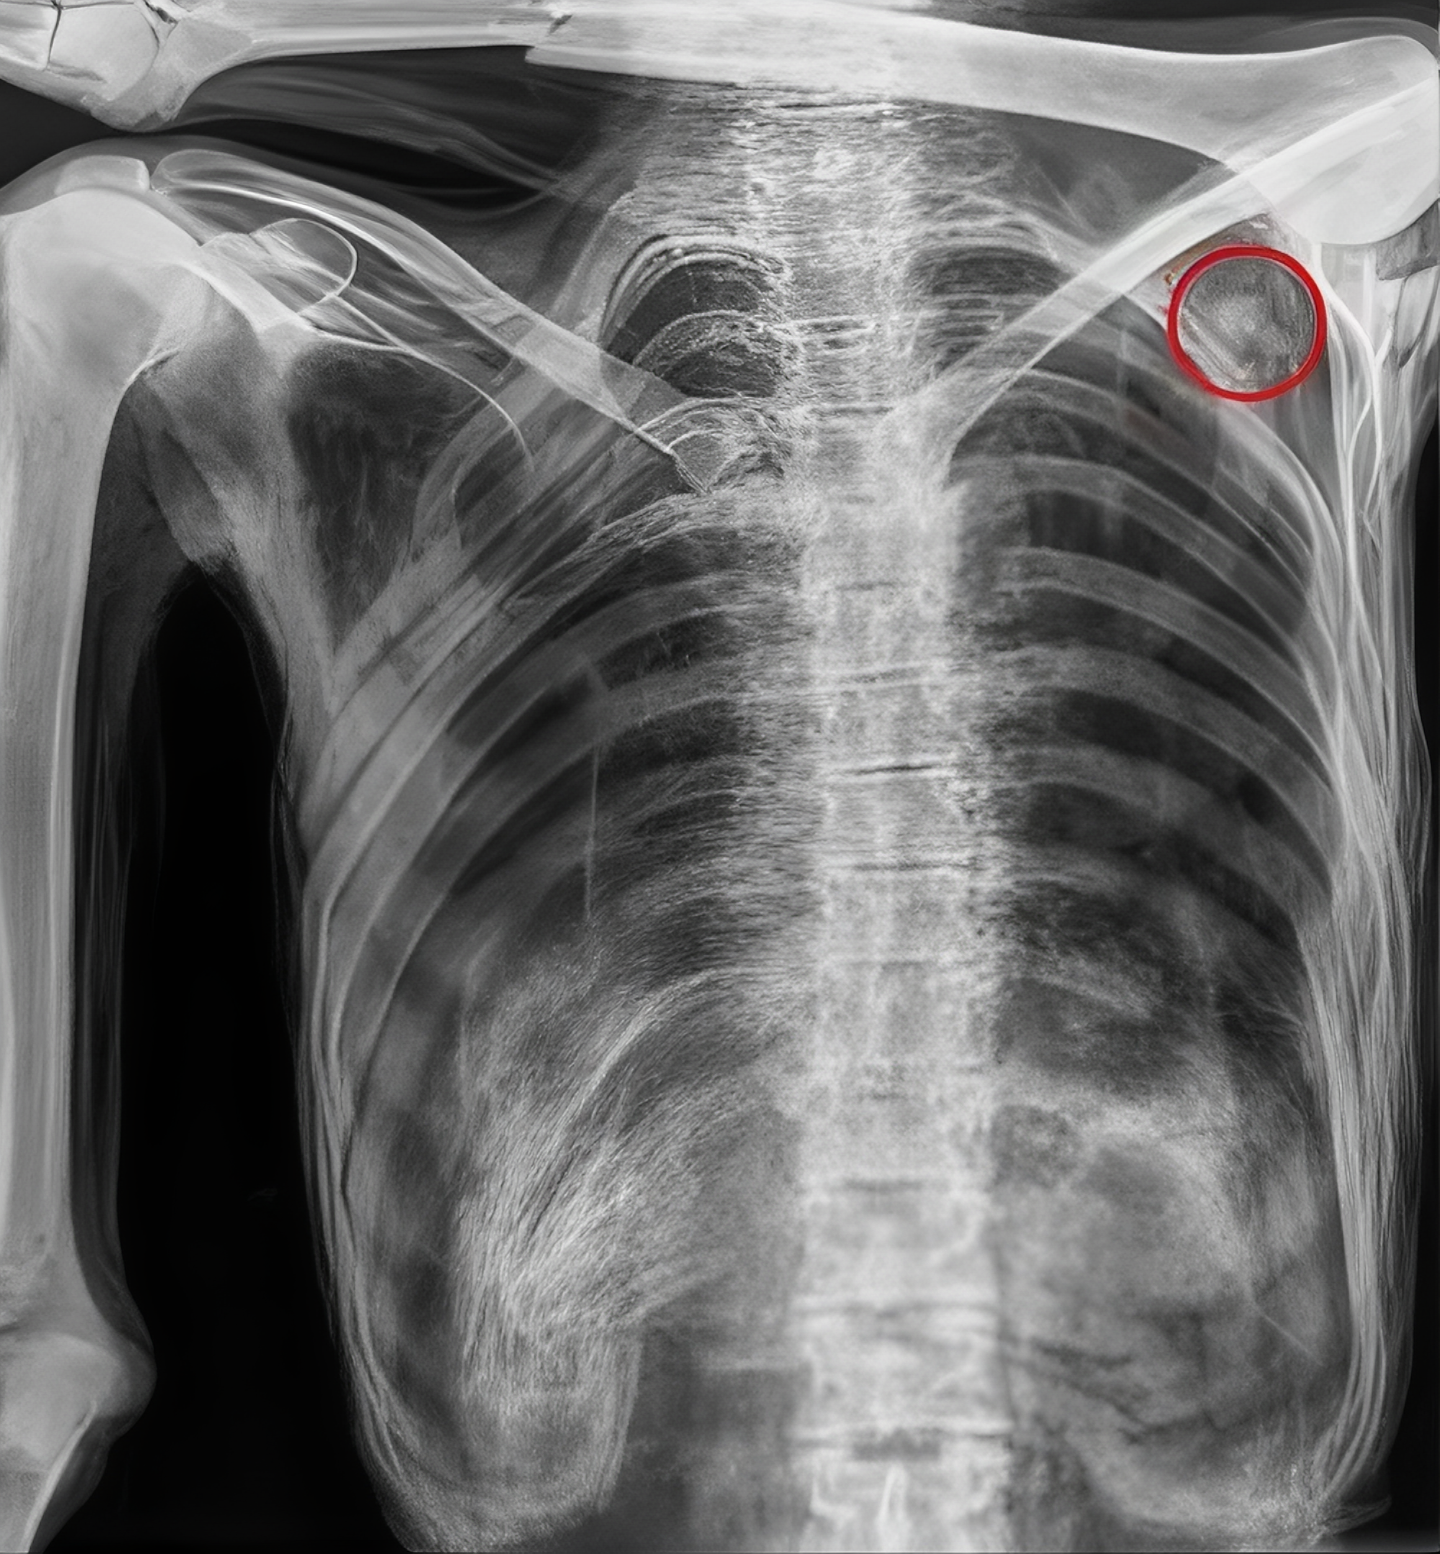

발견된 지 10년이 되던 2001년, 볼차노병원 방사선과 의사인 폴 고스트너 (Paul Gostner)는 외치에 대한 X선 검사를 시행하였는데 여기서 매우 수상한 소견을 발견한 것이다.

외치의 가슴 왼쪽 부분에서 정상적 소견이라고 볼 수 없는 음영을 찾았는데 그가 보기엔 아무리 봐도 인공물 같았다.

외치에 대한 CT 검사에서는 수상 한 부분이 더 두드러졌다.

그의 왼쪽 견갑골 부분에서 2 센티 정도 폭의 구멍이 발견된 것.

이 구멍은 그의 왼쪽 폐 언저리까지 뻗어 있었다.

이 조사에서 확인 된 것은, 외치의 몸안에 남아 있는 것은 돌로 만든 화살촉.

아마도 그는 죽기 전 누군가가 쏜 화살에 맞았을 터인데 그 뚫고 들어간 양상을 보면 왼쪽어깨 빗장밑동맥 (subclavian artery)을 건드렸을 것이다.